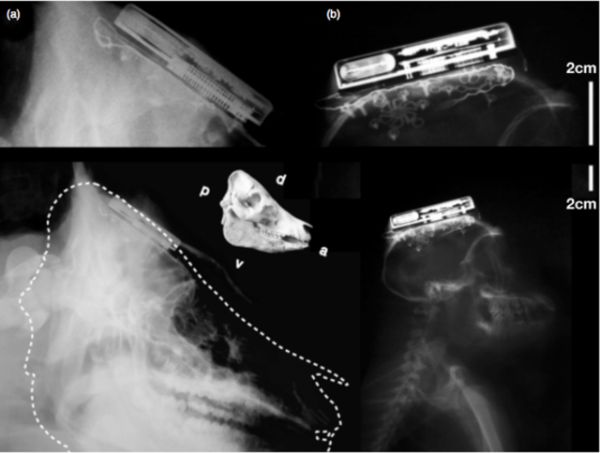

據(jù)外媒報道,近日,來自布朗大學的研究人員研發(fā)出了全球首個通過無線方式連接的腦機接口。雖然早前也曾經(jīng)出現(xiàn)過多種腦機接口,但它們全都無法通過無線連接,所以常常導致穿戴者的行動受限。而現(xiàn)在由布朗大學研發(fā)的腦機接口將打破這一局限。

據(jù)介紹,這個無線腦機接口個頭只有一個火柴盒那么大,它可以放在穿戴者的頭骨進行檢測。它將可以將檢測到的數(shù)據(jù)傳輸給在1米開外的電腦。而安放在其中的200mAh鋰離子電池可以讓這個設備續(xù)航7個小時。